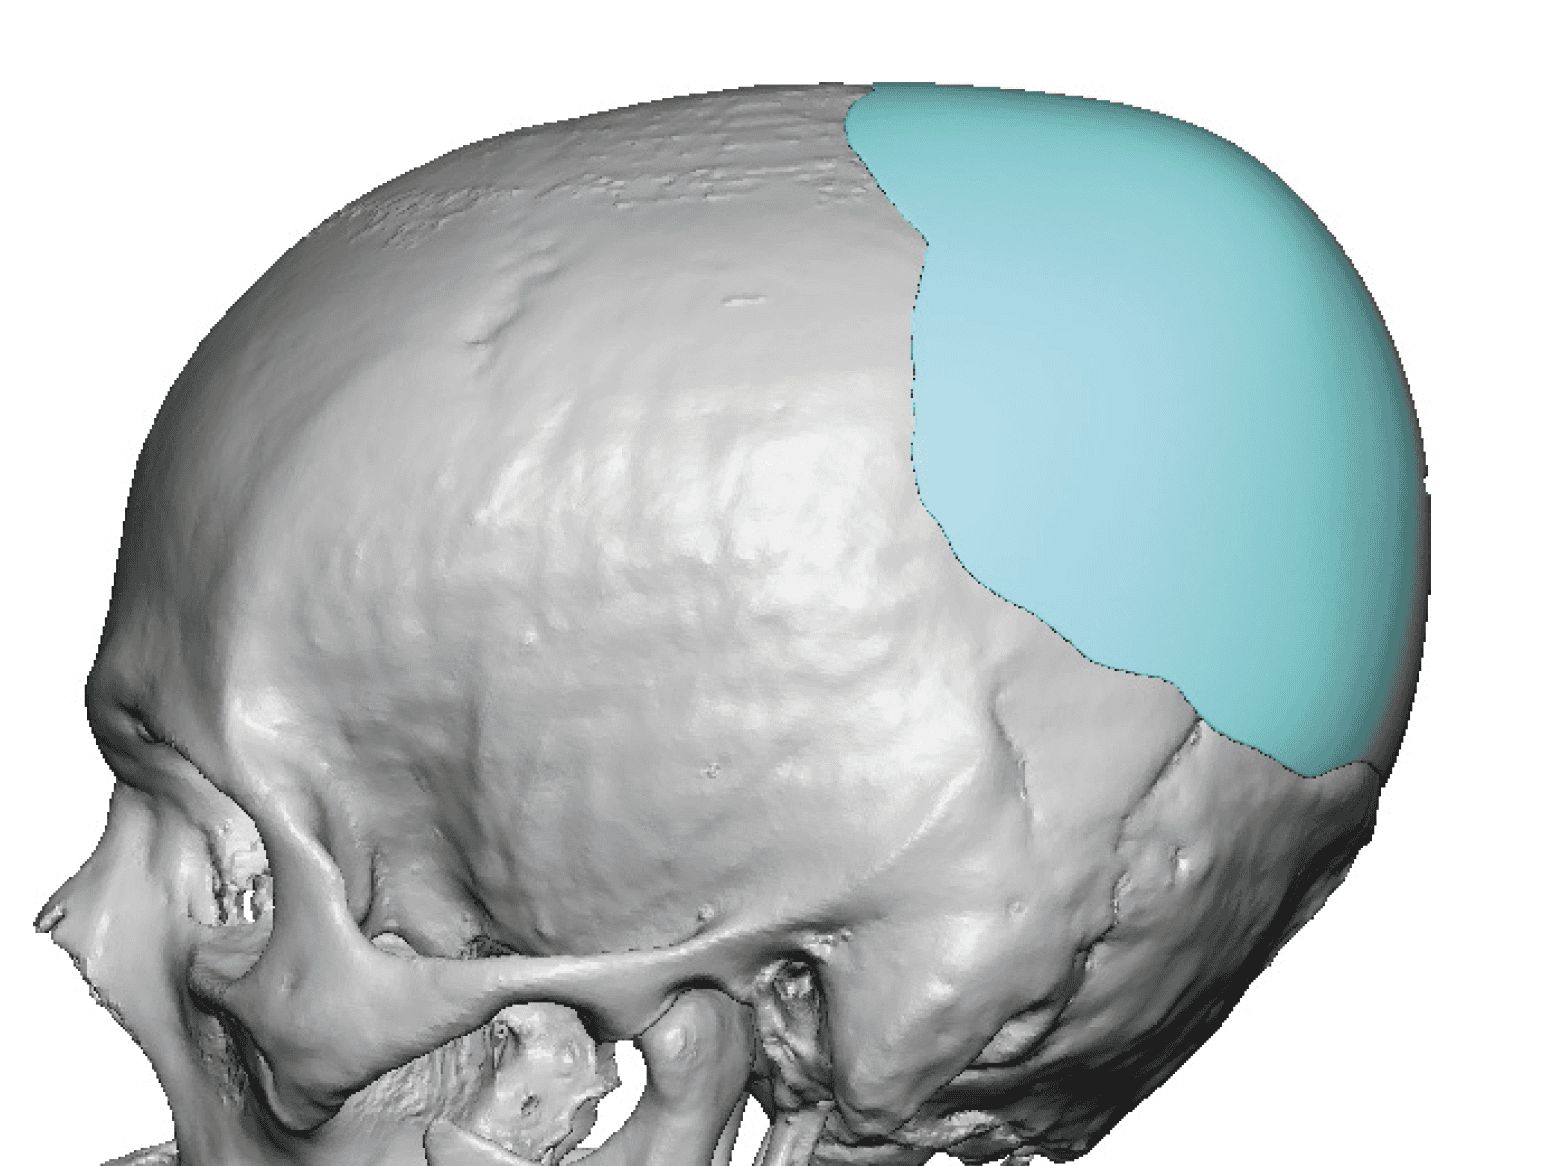

Patient 28

Desire for rounder shape to the top of the head from a congenital parasagittal deficiency skull shape.

Custom skull implant designed to fill in the parasagittal deficiencies.

Desire for rounder shape to the top of the head from a congenital parasagittal deficiency skull shape.

Custom skull implant designed to fill in the parasagittal deficiencies.